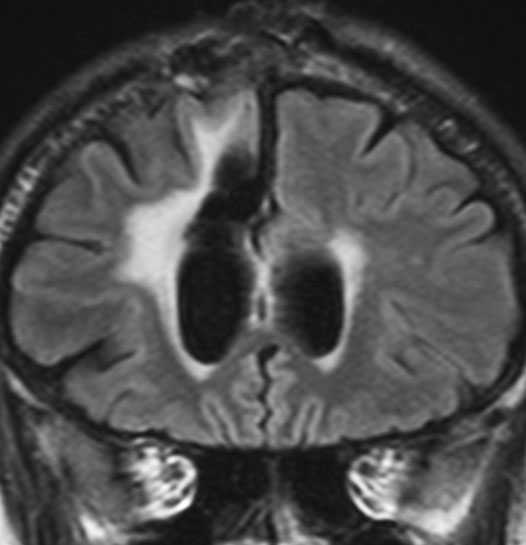

2000年頃の例です。てんかんで発症した20代の女性です。左前頭葉のグリオーマで,手術でほとんどで摘出 subtotal removalして,深部白質に残った病変を経過観察しました。MRIは術後のものです。Ip, 19qはFISHで欠失なし。MIB1は1-2%と低く,MGMTメチレーションなし,diffuse astrocytoma WHO grade 2と組織診断されました。大学病院でしたが当時はIDH遺伝子診断はしておらず,びまん性星細腫グレード2でした。これもまた当時の標準的な考えで,進行があるまでは経過観察としました。

2年後に急激な進行 rapid progressionしました。ガドリニウム増強所見も出現しました。IMRTで59.4Gy/27分割の放射線治療とテモゾロマイド化学療法をしましたが,腫瘍は抑制できませんでした。

放射線治療後も進行して,白質に沿った浸潤伸展をしました。脳幹部橋の右側まで浸潤 invasionしています。この伸展は星細胞系腫瘍の特徴でもあります。

2016年分類では,diffuse astrocytoma WHO grade 2です。しかしこれはおそらく,2021年分類では IDH wild-type astrocytoma grade 4とされます。